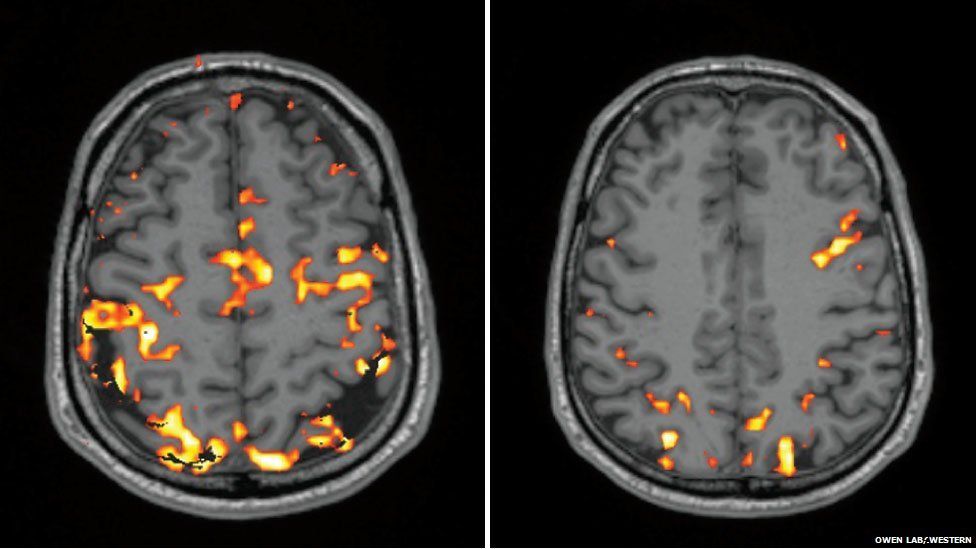

Brain-cleaning sleeping cap gets US Army funding